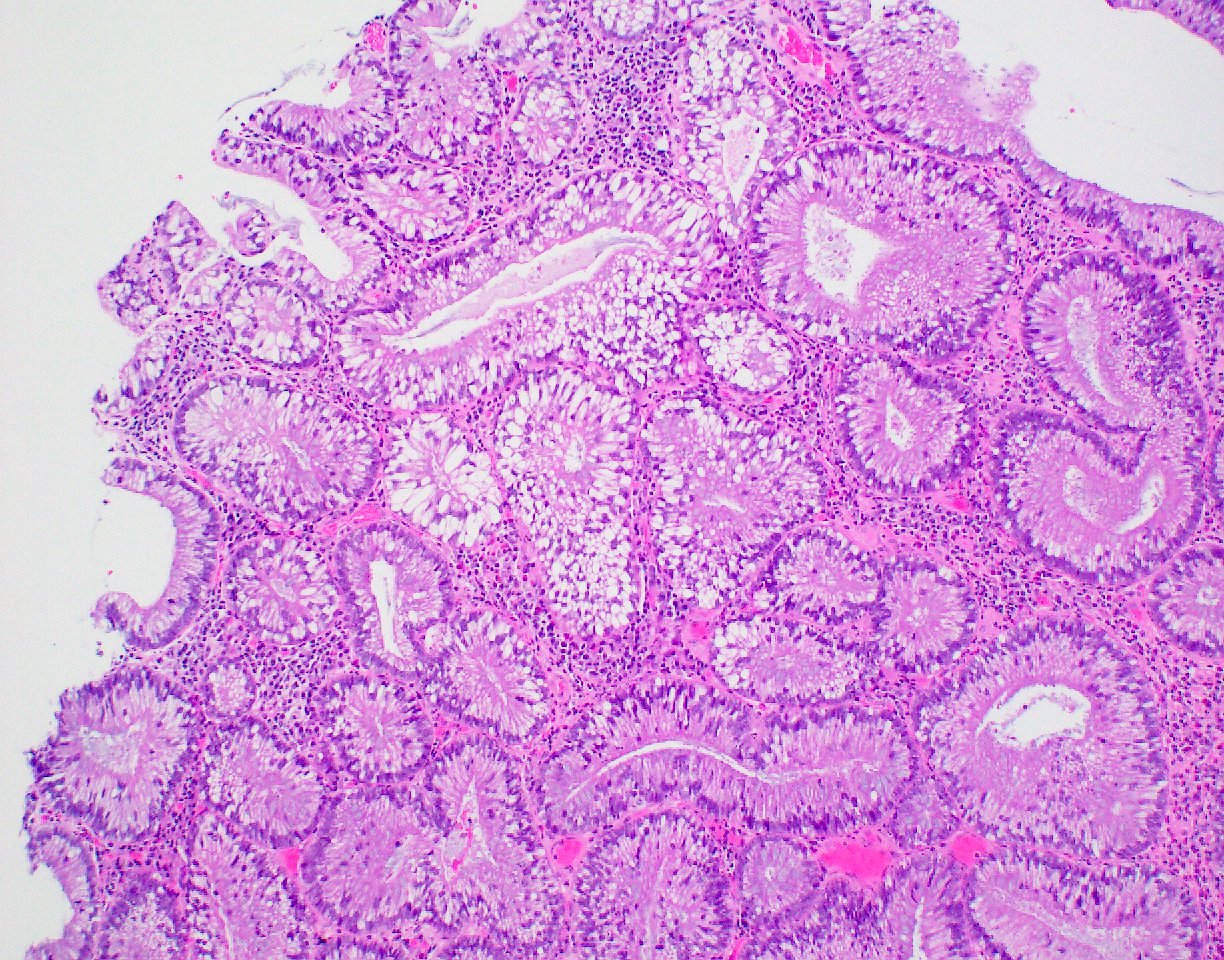

Microscopic (histologic) description

- Polypoid colonic mucosa covered with dysplastic epithelium comprised of hyperchromatic, elongated nuclei arranged in a pseudostratified manner

- Dysplasia is typically low grade but may also be high grade, with architectural (cribriforming, luminal necrosis) and cytologic changes (vesicular chromatin, nucleoli, loss of basal polarity)

- Abrupt transition from normal to dysplastic mucosa is commonly present

- Variable amounts of mucin loss

- Metaplasia may be present: osseous, squamous or Paneth cells (J Clin Pathol 2005;58:220, J Surg Oncol 1984;26:130)

- Pseudoinvasion can mimic progression to adenocarcinoma but displaced glands are benign and surrounded by lamina propria and often hemosiderin (Mod Pathol 2015;28:S88)

- May rarely show clear cell features (Am J Surg Pathol 2010;34:1344)

Microscopic (histologic) images

Contributed by Andrew L.J. Dunn, M.D. and Christopher Hartley, M.D.